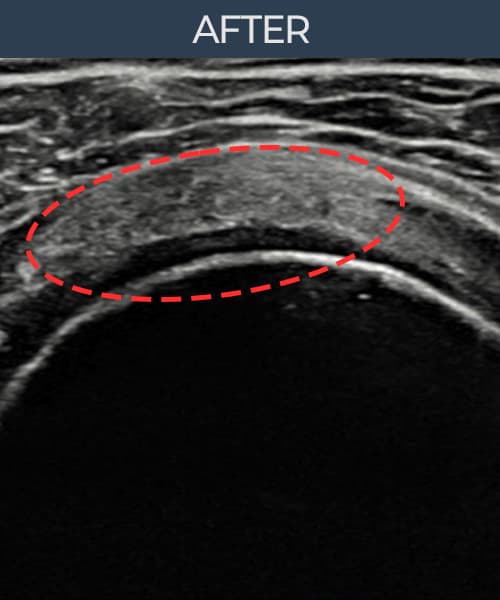

左侧 冈上肌腱 石灰化肌腱炎

9mm × 7mm